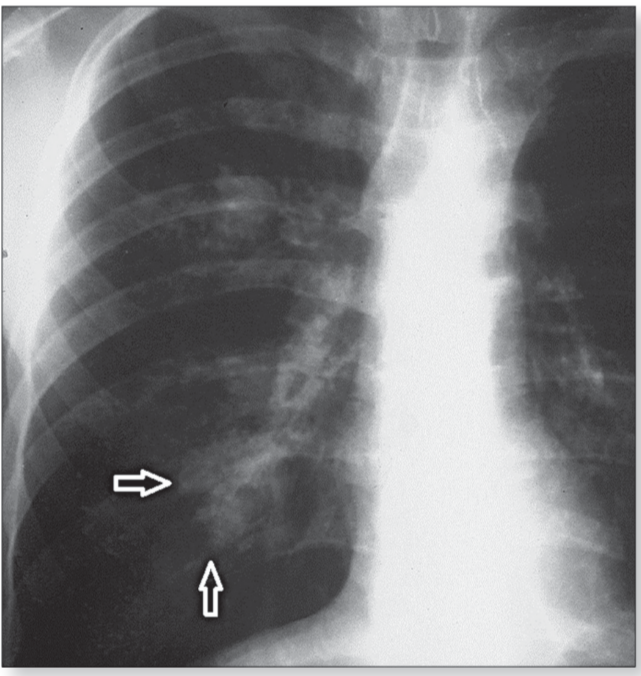

Signo del seno profundo